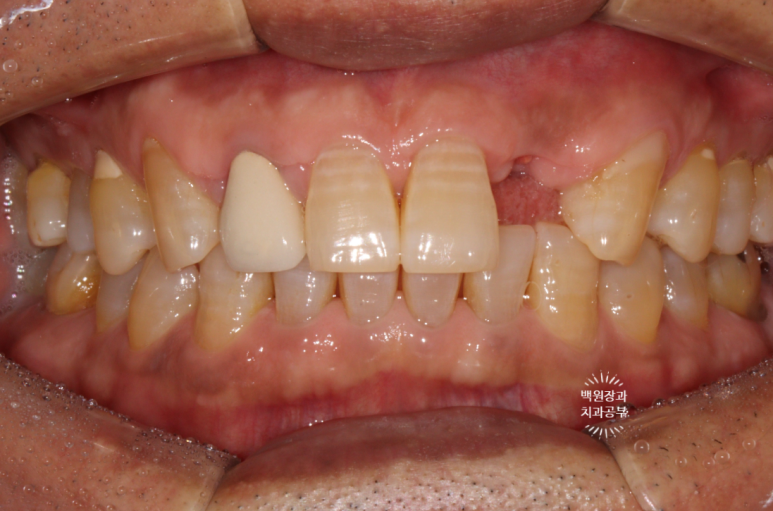

왼쪽 위 어금니를 치료받은지 2년 정도 되었는데,

자기 치아에 염증이 생겨서 빼야한다고 들었어요.

작년 말 저희 병원에 내원하셨던 중년 여성 환자분입니다.

왼쪽 위 어금니에 염증이 있어서 빼야한다고 들으셨다는데...

왠걸! 이런 보철물을 내가 직접 보게 되다니~

하나는 자연치아, 하나는 임플란트가 한 개의 보철물로 연결되어 있더라구요.

정확히 브릿지 (bridge)라고 부르지는 않지만, splinted crown 이라고 부릅니다.

교수님들 말씀이 맞았네요... 결국 자기 치아가 완전히 고장나버렸고,

주변은 염증이 가득 형성되서 잇몸뼈가 모두 사라져 버렸습니다.

처음 오셨을 때 입 안 사진으로 보면, PFM 크라운 두 개가 붙어있는 형태.

즉, splinted PFM crown 형태로 제작이 되어 있었어요.